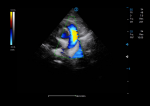

For Cardiac Assessment

Adaptive TDI assesses muscle wall characteristics throughout the cardiac cycle with consistent measurement via self-adaptive tracing technology.

Color M & AMM are specialized for detecting subtle changes, monitoring during surgery, and assessing cardiovascular function and injury severity.

Triplex integrates anatomical imaging, dynamic flow observation and spectral analysis for a comprehensive assessment on vascular disease from multiple perspectives. PW auto correlation being activated during triplex on is to help present another real time quantitative analysis.

PW mode provides accurate hemodynamic and spectral information to detect subtle changes in blood flow and enable quantitative measurement.

CW mode sensitively detects and visualizes high-velocity blood flow signals, which is helpful for the diagnosis of early vascular disorders in animals.